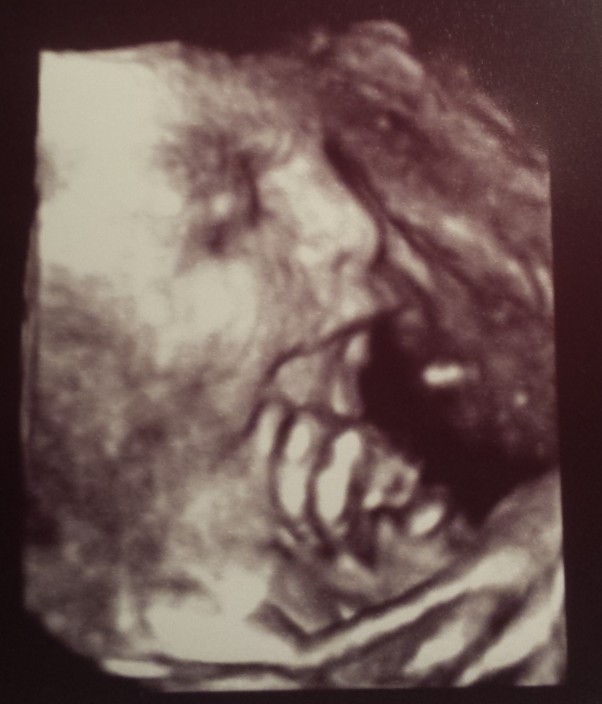

Córeczko jak Ty już duża jesteś :* ale i moja mała wstydnisia :) nie lubisz się pokazywać i zawsze udajesz ze spisz wtedy kiedy jest badanie :) moja najukochańsza maleńka księżniczka - Kochamy Cię najmocniej na świecie.